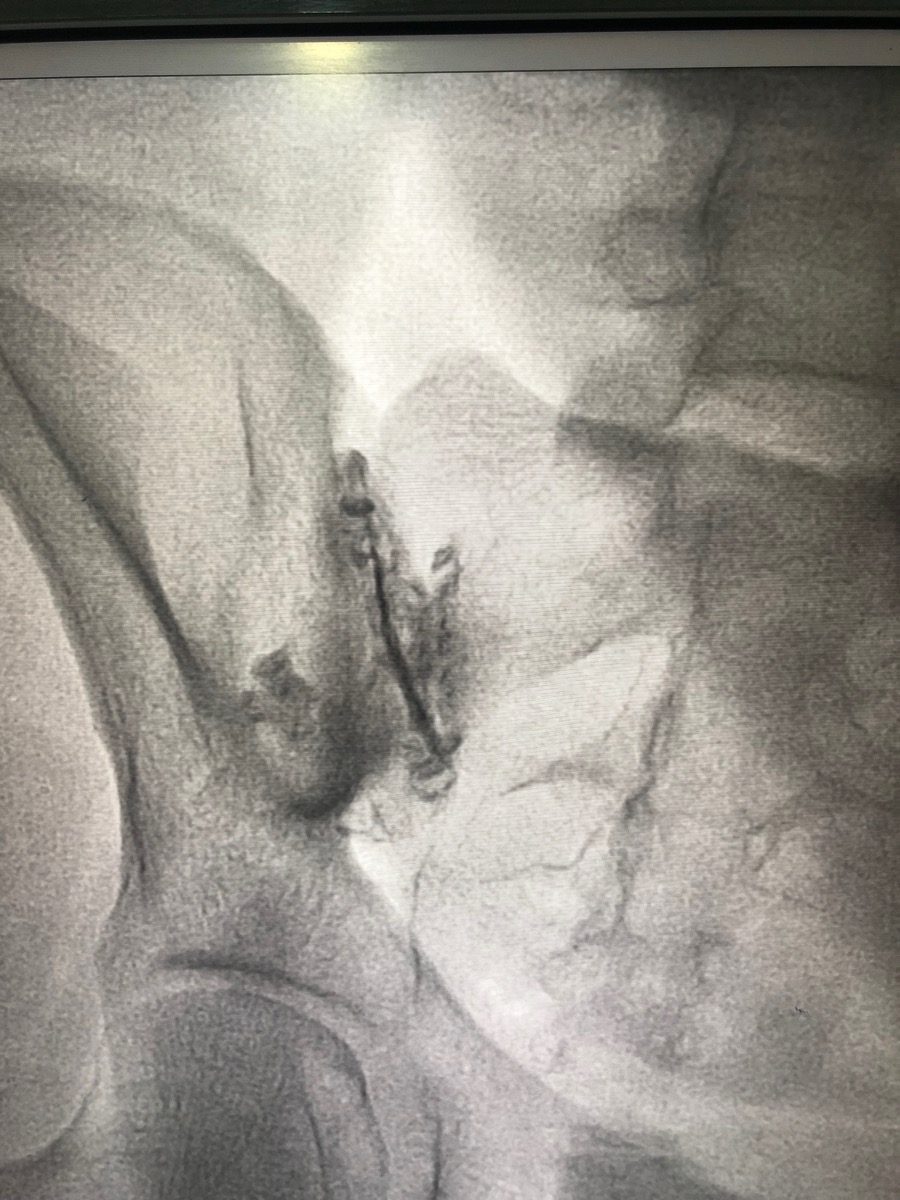

How is a sacroiliac joint injection performed?

You lie face-down on the procedure table. The skin over your lower back and buttock area is cleaned and numbed. Under fluoroscopy (live X-ray) guidance, a thin needle is guided precisely into the SI joint. A small amount of contrast dye is injected to confirm the needle is inside the joint, then the steroid and anaesthetic are delivered. The procedure takes about 15–20 minutes.